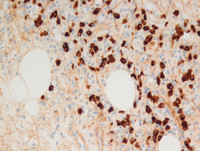

Figure 3: Breast lump-S-100

Nuclear and cytoplasmic S-100 protein expression is typical for these histiocytes (as opposed to reactive histiocytes which do not express S100). Also note the highlighted entrapped inflammatory cells in their cytoplasm, which are negative for S-100 protein (black arrow). Additionally, histiocytes in RDD are positive for CD68 and negative for CD1a expression, which helps differentiate this condition from other histocytic disorders like Langerhans cell histiocytosis and Erdheim-Chester disease.